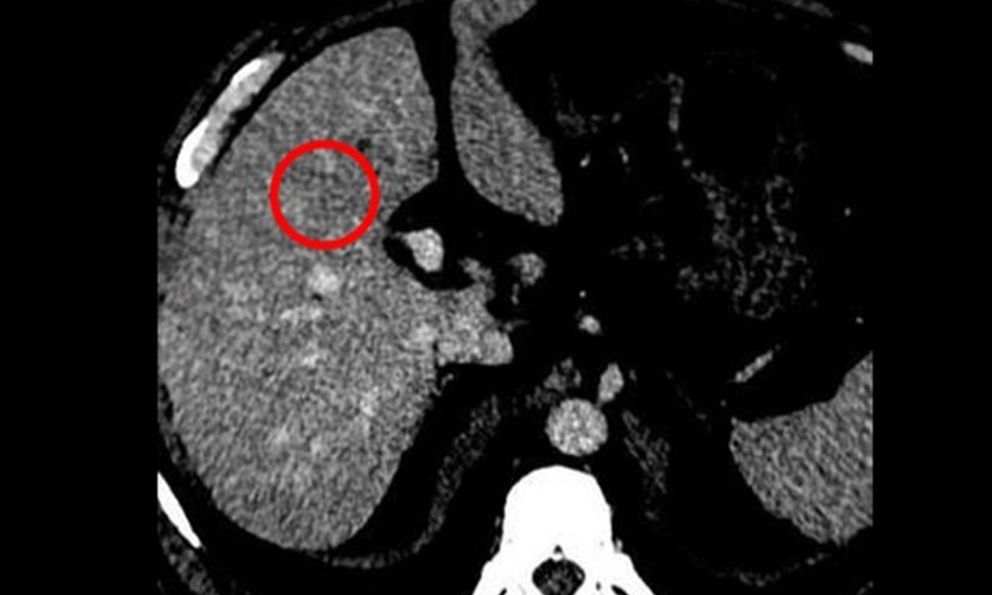

Kết quả chụp CT cho thấy gan xuất hiện khối tổn thương kích thước khoảng 22 x 24 mm cùng một số nốt nhỏ khác. Sinh thiết sau đó xác nhận ông mắc Ung thư gan giai đoạn sớm.

May mắn được phát hiện ở giai đoạn sớm, ông Phi được chỉ định điều trị bằng phương pháp Đốt u gan bằng sóng cao tần (RFA) – kỹ thuật sử dụng nhiệt để phá hủy tế bào ung thư. Tuy nhiên, các bác sĩ nhấn mạnh, điều trị thành công không đồng nghĩa với “khỏi bệnh hoàn toàn”, người bệnh vẫn phải tái khám định kỳ để theo dõi nguy cơ tái phát.